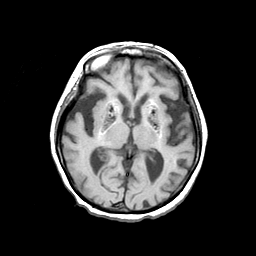

Basal Ganglia Calcification: T1-weighted MR -- Slice #9

[Home][Help][Clinical] Slice 9